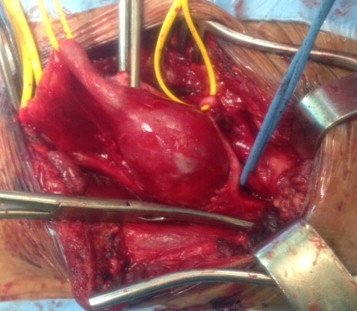

L’anévrisme aortique est une maladie de l’aorte consistant en une dilatation de cette dernière. Elle peut concerner n’importe quel segment de ce vaisseau. La forme la plus fréquente est l’anévrisme de l’aorte abdominale en dessous des artères rénales